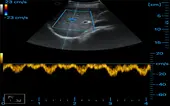

Kidney + CF + PW

Liver + CF + PW